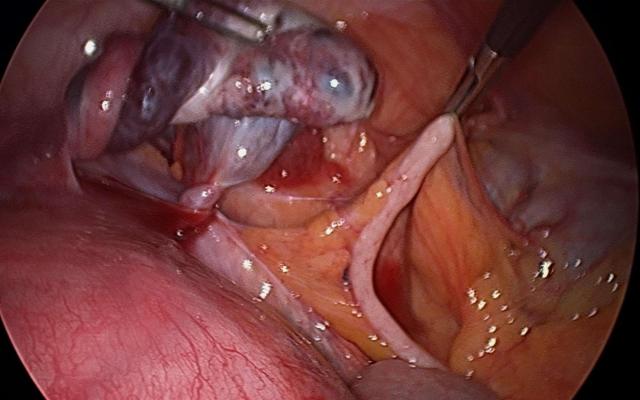

Een 33-jarige vrouw (gravida 2, para 1) meldde zich via de huisarts op de SEH met een acuut ontstane progressieve buikpijn sinds 1,5 uur. Zij was 20 weken zwanger en had een blanco voorgeschiedenis. Zij was misselijk en kon enkel met opgetrokken benen liggen. Er was geen sprake van vaginaal bloed- of vochtverlies. Bij inspectie oogde de patiënte niet ziek, maar had veel pijn, met name rechtsonder in de flank, doortrekkend naar rechtsonder in de buik. Haar temperatuur bedroeg 37,1°C, de polsfrequentie 64/min en de bloeddruk 110/62 mmHg. Bloedonderzoek liet een CRP-waarde van 15 en leukocytenaantal van 15 zien…